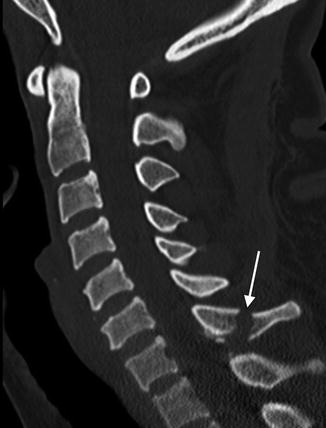

Sagittal CT of the cervical spine displays a mild distracted fracture of the C7 spinous process (arrow) without malalignment in a 35-year-old patient following a motor vehicle accident. Of note, the intracanalicular contents include the spinal cord that cannot be reliably assessed on this image

Sagittal T2-weighted MR image reveals abnormal cord signal indicative of cord contusion/edema (arrow) that was not apparent by CT